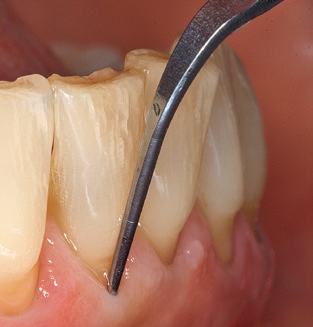

Die gute Ausleuchtung des Arbeitsfeldes stellt eine wesentliche Erleichterung dar. Bei dem von den Autoren genutzten System ist dies gelungen, indem ein 5facher LEDRing in das Handstück integriert wurde. Natürlich werden für dieses System unterschiedliche Arbeitsspitzen für die jeweiligen Indikationsbereiche angeboten. Eine gerade, universell einsetzbare Spitze ist das Basisinstrument zur maschinellen Instrumentierung natürlicher Zähne (Abb. 5a und b). Für schwer zugängliche Bereiche im Seitenzahnbereich werden gebogene Spitzen angeboten, die auch einen Zugang zu freiliegenden Furkationen ermöglichen (Abb. 6).

Unerlässlich für die UPT implantat prothetisch versorgter Patienten sind natürlich Arbeitsspitzen für die Reinigung von Implantatoberflächen. Der Implantatreinigungsaufsatz des hier verwendeten Systems zeichnet sich dabei durch eine spitz zulaufende sechskantige konische Form aus. Dieses Design erlaubt ein leichtes atraumatisches Eindringen in die periimplantäre Tasche und zeigt eine gute Reinigungsleistung (Abb. 7).